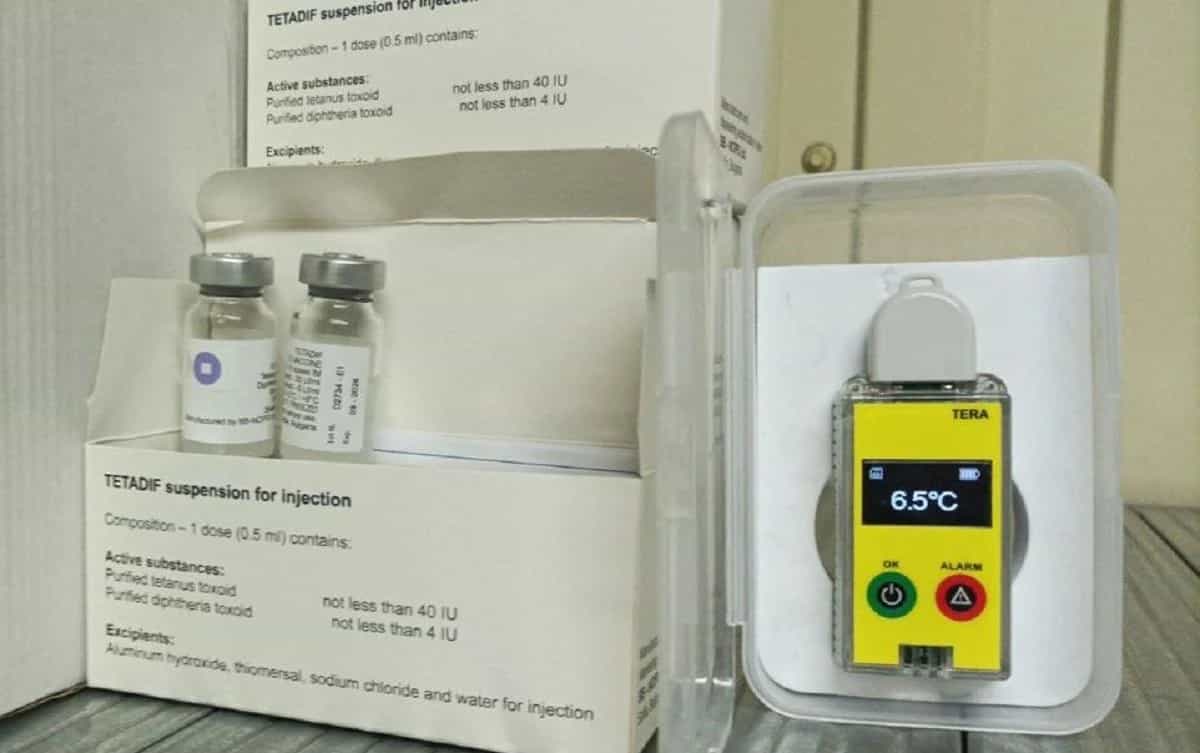

В Україну завезли вакцину проти небезпечних хвороб